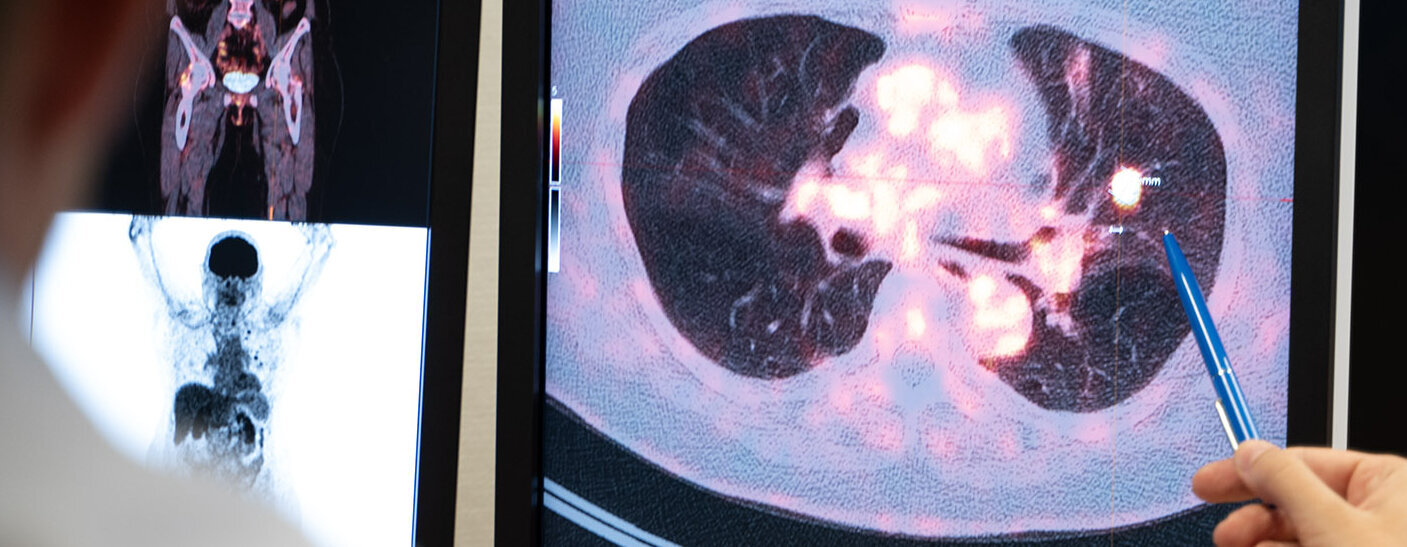

Die FDG-PET/CT ist eine wichtige Bildgebungsuntersuchung in der Klinik für Nuklearmedizin am UKS. Sie wird genutzt, um Funktionen und Stoffwechselprozesse im Körper auf molekularer und zellulärer Ebene zu betrachten. Besonders bei der Diagnose und Abklärung von Krebserkrankungen spielt die FDG-PET/CT eine zentrale Rolle.

FDG steht für Fluordesoxyglukose, eine radioaktiv markierte Form von Glukose. Bei der FDG-PET/CT werden zwei verschiedene bildgebende Verfahren kombiniert: die Positronen-Emissions-Tomografie (PET) und die Computertomografie (CT). Diese Kombination ermöglicht es, präzisere diagnostische Ergebnisse zu erzielen, da sie sowohl funktionale als auch anatomische Informationen liefert.

Bei allen Erkrankungen wird der Patientin oder dem Patienten für die PET-Untersuchung ein schwach radioaktiv markiertes Medikament in die Armvene gespritzt, das sich im Körper verteilt und dabei von den Zellen aufgenommen wird. Am häufigsten wird ein radioaktiv markierter Zucker eingesetzt. Nach einer Wartezeit von 30 bis 90 Minuten, während der sich das radioaktive Medikament im Körper verteilt, werden PET/CT-Bilder des gesamten Rumpfs aufgezeichnet. Die Aufnahmen erfolgen im Liegen und dauern etwa 30 Minuten. Bei bestimmten Fragestellungen kann es auch notwendig sein, ein zusätzliches Röntgenkontrastmittel einzusetzen, das über eine Pumpe in die Armvene gespritzt wird.